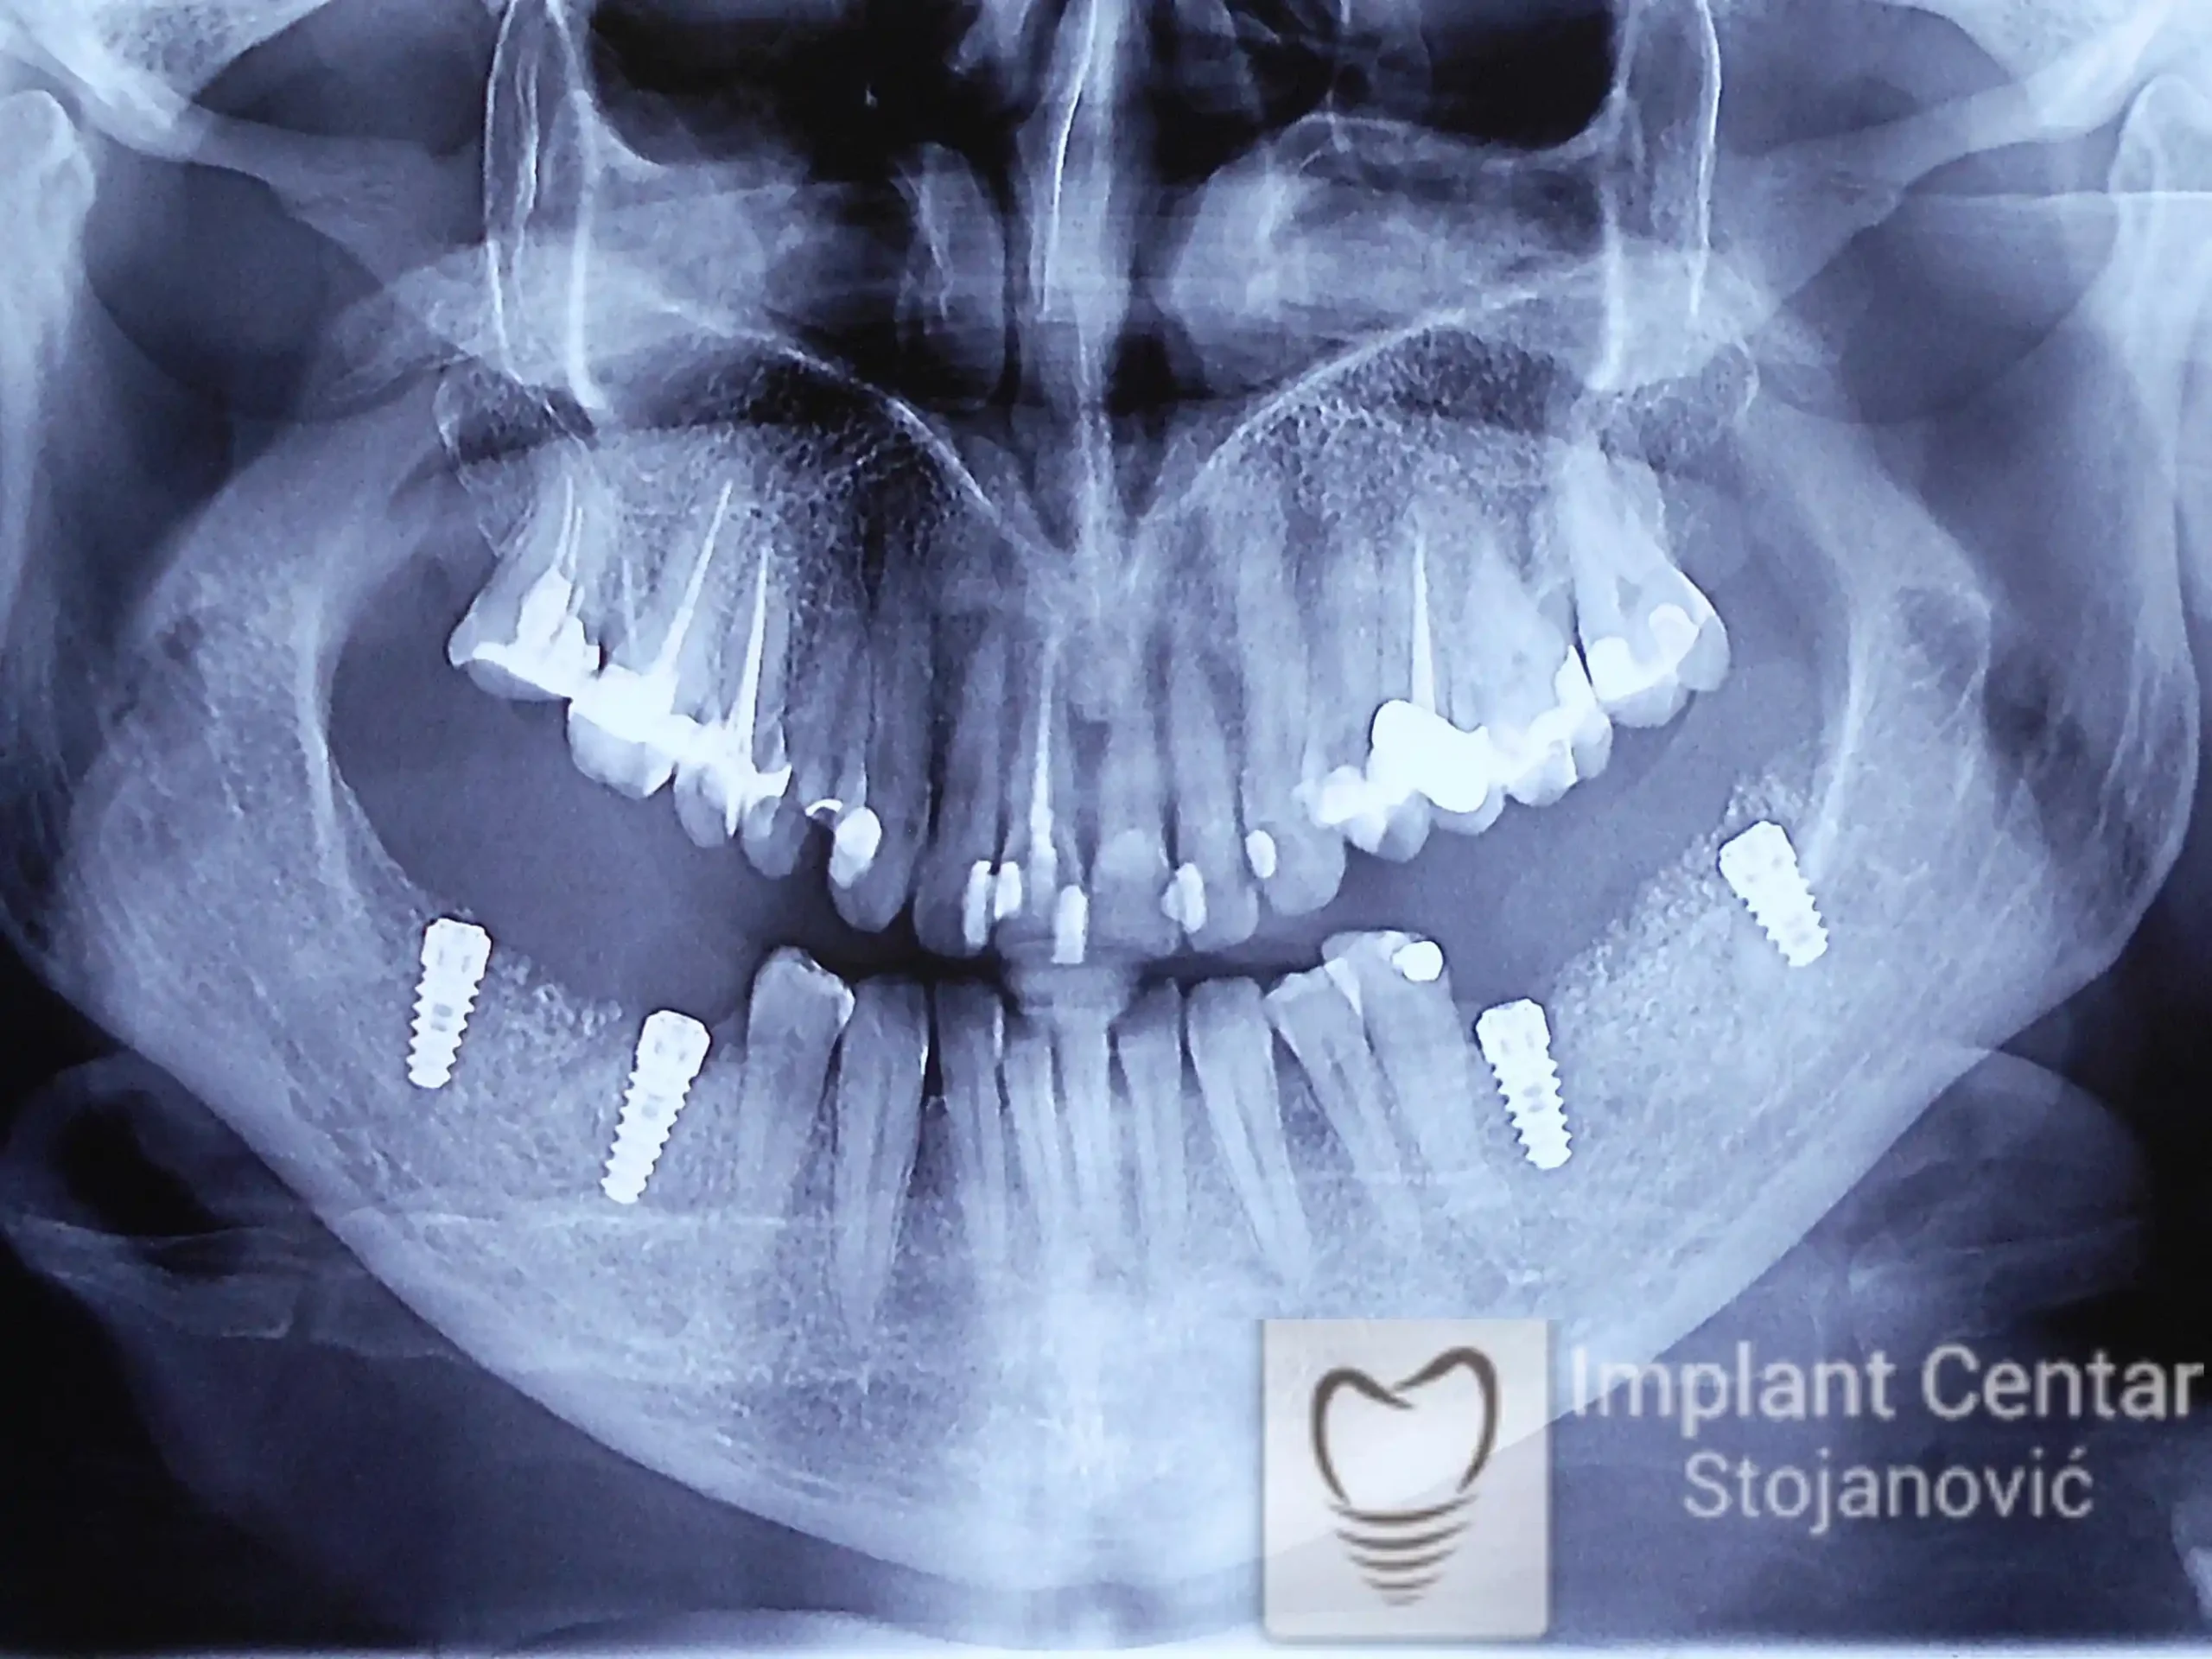

Na slici 1. i slici 2. prikazan je izgled pacijenta pre početka terapije – klinički i rendgenološki.

Nakon vađenja zuba, ugrađeni su implantati. Na slici 3 prikazan je ortopan snimak sa ugrđenim implantatima. Tokom perioda osteointegracije, pacijent je bio zbrinut fiksnim privremenim krunicama na implantatima, koje su izrađene samo dva dana nakon hirurške intervencije.